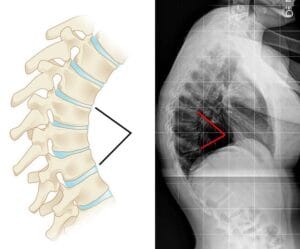

While the thoracic spine naturally curves between 20 and 45 degrees, certain postural or structural abnormalities can increase this curvature beyond normal limits. Known medically as hyperkyphosis when it exceeds 50 degrees, this excessive curvature is often simply referred to as kyphosis by doctors to describe the clinical condition resulting in a rounded upper back. The severity of kyphosis can vary. Generally, more pronounced curves lead to a more serious condition. Milder kyphosis may cause minimal discomfort or none at all, while more severe cases can result in noticeable spinal deformity, often producing a visible hump on the upper back.